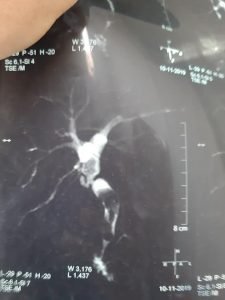

هذه صور رنين مغناطيسى علي القنوات المرارية لحالة تم لها إجراء عملية استئصال المرارة بالجراحة منذ ٢٠ سنة في مستشفى آخر وقد حدث اصابة جزئية في جدار القناة المرارية وقد وضع الجراح المعالج للحالة في ذلك الوقت أثناء العملية قسطرة في القناة المرارية لتصريف السائل المراري وقد حدث ضيق شديد في القناة المرارية مع تكوين حصوات في القناةالمرارية وصفراء انسدادية بعد ٢٠ سنة من إجراء إستئصال المرارة .

وهذا يبين أنه حتي في حالة الإصابات الجزئية للقناة المرارية أثناء عملية استئصال المرارة بالمنظار أو الجراحة يحتاج المريض إلي متابعة طويلة الأجل وذلك للإكتشاف المبكر للضيق و الذي قد يحتاج إلى عملية اصلاح للقناة المرارية بتوصيلها بالأمعاء أو حسب مايراه الأطباء المتخصصون.

MRCP images showing late marked bile duct stricture after open cholecystectomy done 20 years ago in another Hospital. Partial biliary injury occurred during the operation as the Patient has mentioned and the surgeon managed the case at that time by inserting biliary tube drainage from the site of bile duct injury. postoperatively there was bile leak aroud the drains that resolved spontaneously after about one month. Recently the Patient developed obstructive jaundice and ascending cholangitis and presented to us for definitive management .

The message is that all cases with bile duct injury need long term follow up even after partial bile duct injury that has been managed by biliary tube drainage as bile duct stricture may occur slowly over a long time.

Early detection of iatrogenic biliary stricture is essential and defintive biliary Reconstruction may be needed even many years after the previous biliary procedure.